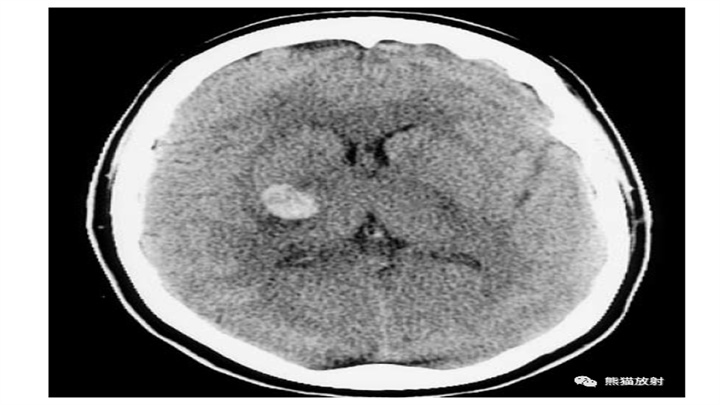

壳核血肿扩散到外囊(2例)。沿前后方向呈典型的细长形。